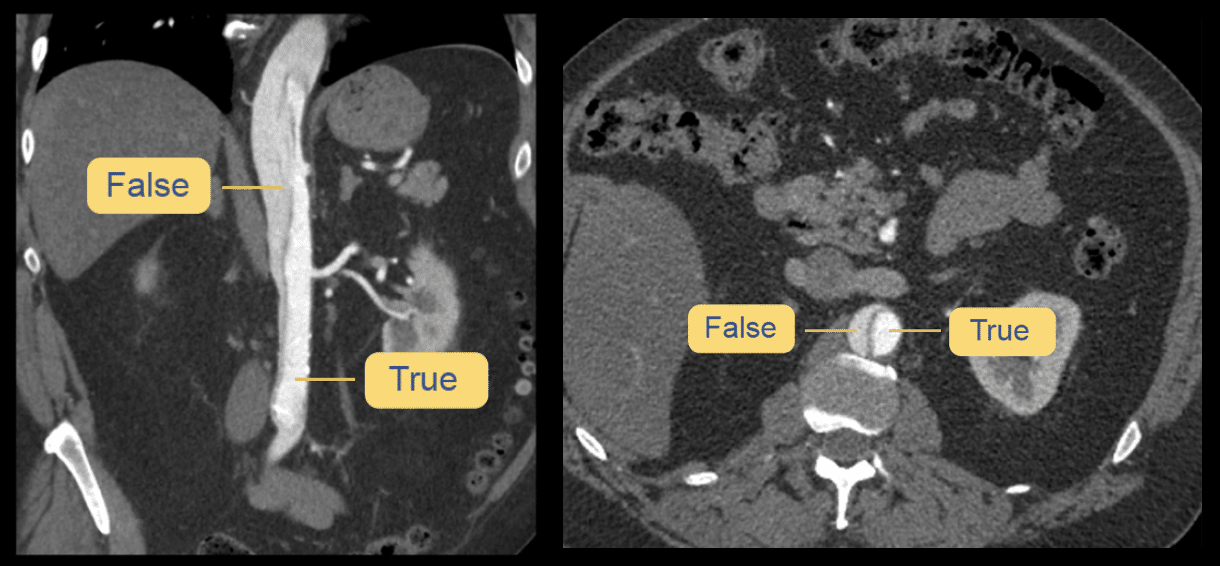

mySurgery | Acute Abdomen。CT of acute abdomen in the elderly | Insights into Imaging。The added value of multidetector CT in the diagnosis of。急性腹症に関するCTの詳細な解説が収められた専門書。- タイトル: CT of Acute Abdomen 第3版- 著者: 荒木 力- 言語: 日本語- 出版社: メディカル・サイエンス・インタ裁断済みのため状態が悪いとしています。ほかの商品とのセットで購入していただける場合値下げ対応いたします。。CT of the Acute Abdomen: GI Applications - Part 1 - YouTube。腰痛 成田崇矢の臨床。【裁断済】心臓血管外科手術 周術期管理のすべて 第2版